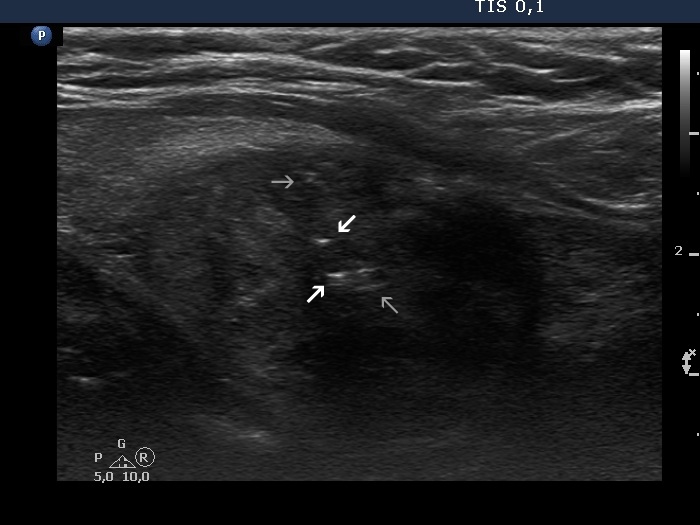

Benign colloid goiter (cytological diagnosis)

The nodule has both pale and bright hyperechogenic lines and granules. Arrowheads point to figures representing the normal architecture of the thyroid while arrows do to thickened connective tissue.